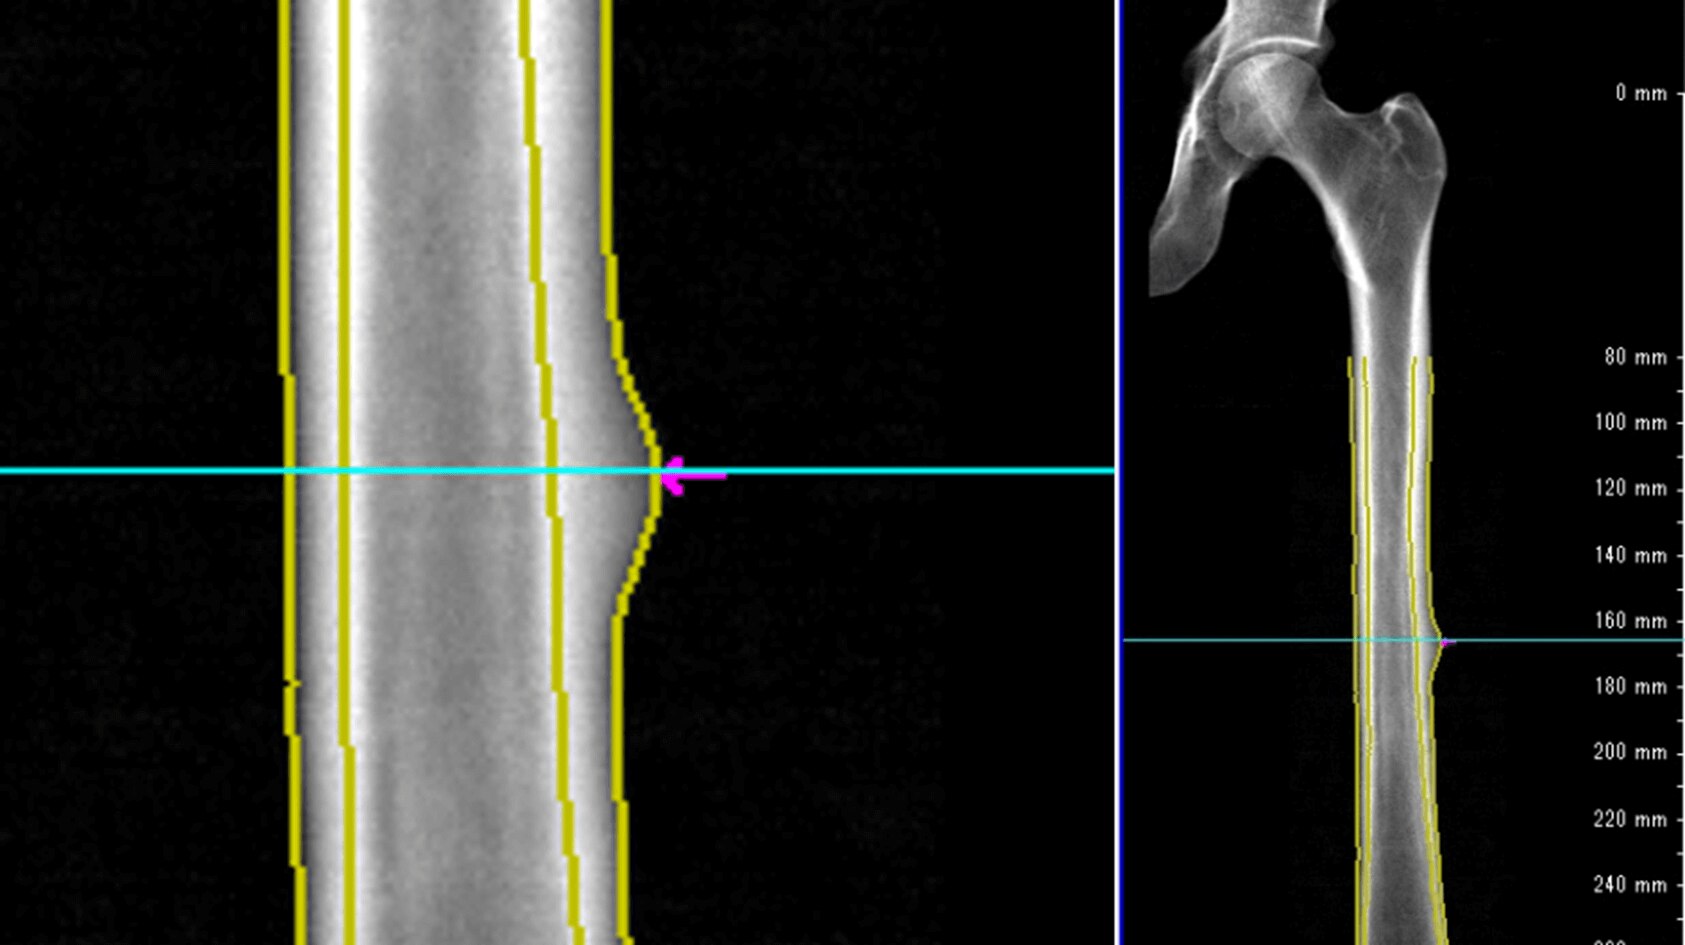

Using ISUOG practice guidelines, SonoLystIR automatically detects recommended views. It identifies anatomy, then selects applicable annotations and measurements. Confirm and data is entered into the Scan Assistant checklist and report, enhancing workflow and reducing variability.